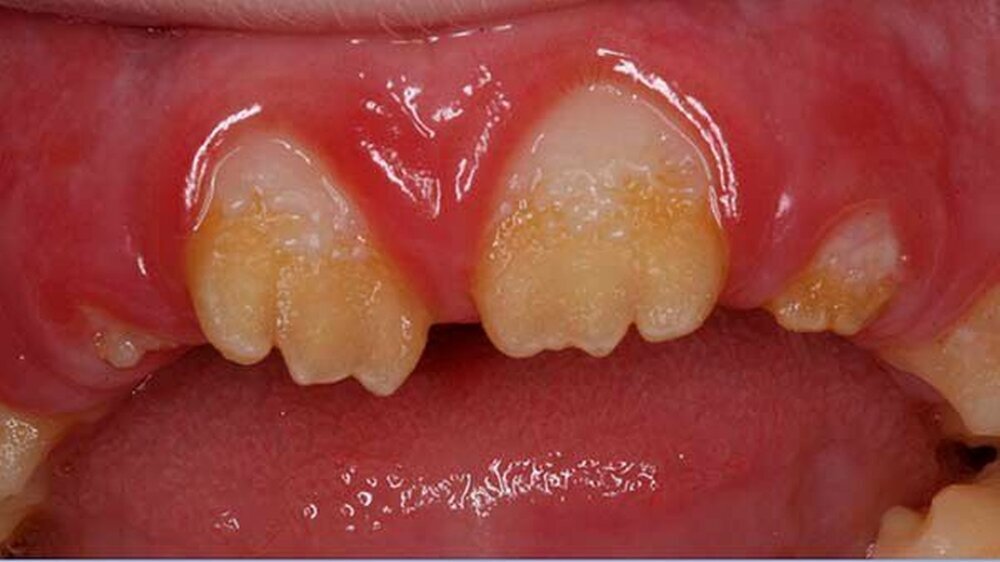

Der klinische Befund zeigte an beiden Dentitionen eine rauhe, zum Teil verminderte, bis fehlende Schmelzdicke und eine teilweise bräunliche Zahnverfärbung. Letztere wurden auch durch exogene Pigmenteinlagerung verursacht (Abbildung 1b und Abbildung 2).